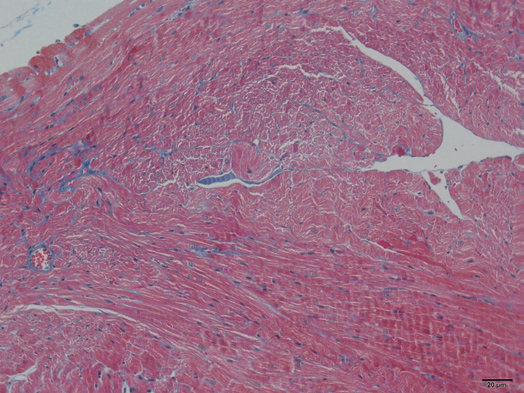

肿瘤病理分析VS心脏组织Masson染色

HEvs组织硬切